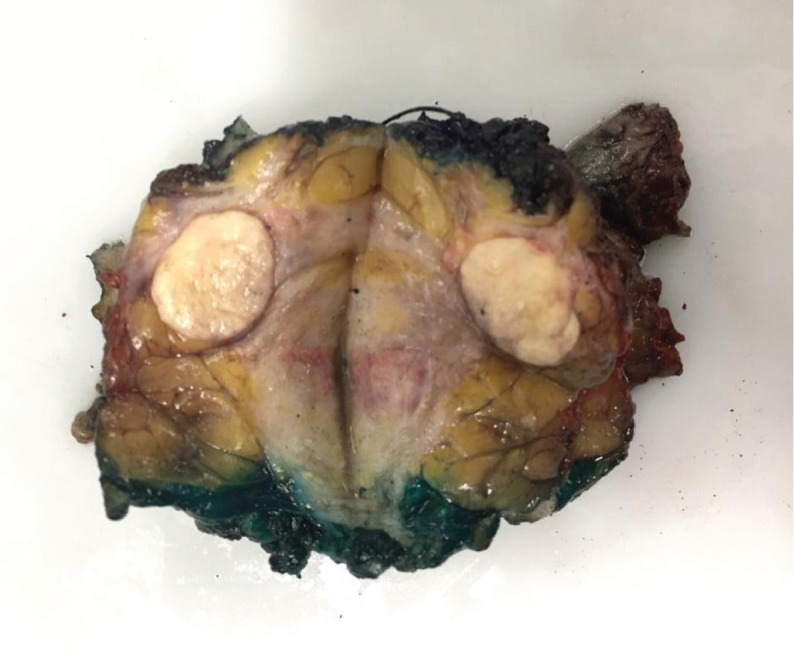

Background: Sebaceous carcinoma of the breast (SCB) is an unusual neoplasm. To the best of our knowledge, only 30 cases have been reported in the literature. Due to its rarity, there is limited knowledge on how to manage patients with SCB. This article aims to describe a case of multicentric sebaceous breast carcinoma in a 33-year-old woman detailing the diagnostic process, historical findings and the treatment approach.

Abstract Image